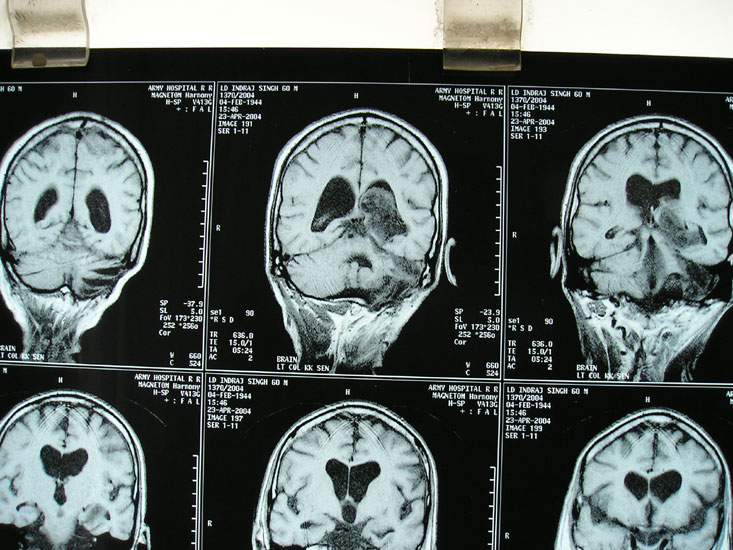

Hydrocephalus

Hydrocephalus is a common problem in the childhood, due to obstruction to the flow of cerebrospinal fluid (‘clear fluid within the brain cavities’). Child presents with an enlarging head, headache, vomiting, drop in school performance. MRI is required to diagnose hydrocephalus, and to ensure that there is no brain tumor causing obstruction. Treatment is insertion of ventriculoperitoneal shunt from brain to the abdomen. In older children, endoscopic third ventriculostomy too can be considered.